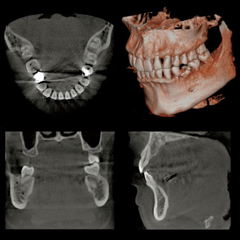

歯科用CT

ベラビューエポックス3Dfは1台でパノラマ撮影、セファロ撮影、CT撮影が可能です。

デジタルテクノロジーを駆使し、より少ないX線照射線量で撮影できる、CT撮影が可能なパノラマX線装置です。

さらに高精細で様々な画像処理により、多角的な診断に役立つことが期待できます。

簡単な位置付けと操作により、Φ40×H40mmの局所領域の撮影から、フルマウス対応のΦ100相当×H80mmのCT画像まで鮮鋭な画像を提供します。